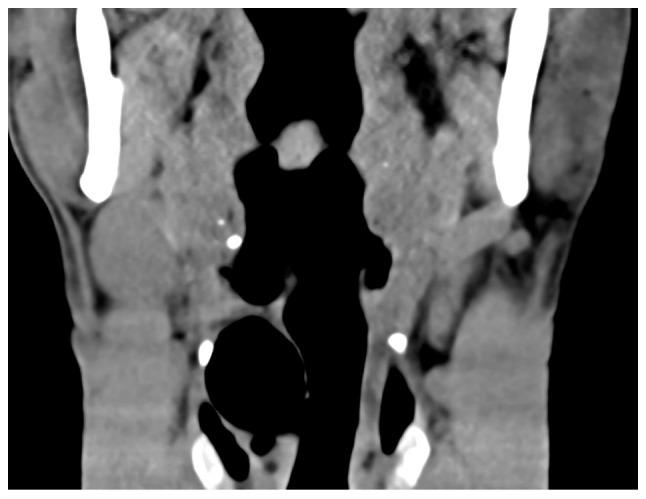

Laryngocele is a rare clinical condition characterized by an abnormal dilation of the laryngeal saccule. The present study focused on two separate cases of diagnosed patients. The first patient suffered from internal laryngocele and complained of hoarseness for almost 1 year. Plasma was used to treat the internal laryngocele and the outcomes were satisfying. The patient did not undergo any tracheostomy due to previous endoscopic surgery. The second patient included in the present study was diagnosed with mixed laryngocele and complained of swelling on the left side of the upper aspect of the neck with considerable pain for >1 month. The patient was prepped for excision by an external transcervical technique under general anesthesia. None of the two patients had any recurrence or other changes during follow-up. The purpose of reporting these two cases of laryngocele was to increase awareness of this condition. Surgery is still the first-line treatment for diagnosed cases, but with the advent of new microscopic techniques, the use of plasma in an inter-pharynx setting has become more common. The results observed after using plasma to treat one internal laryngocele may be relevant to better understanding the application of this method and confirm that it may be a new suitable approach to treat this condition.

喉膨出是一种罕见的临床病症,其特征为喉囊异常扩张。本研究聚焦于两例确诊患者。首例患者患有内喉膨出,主诉声音嘶哑近1年。采用等离子体治疗内喉膨出,效果令人满意。由于先前的内镜手术,该患者未进行任何气管切开术。本研究纳入的第二例患者被诊断为混合型喉膨出,主诉颈部上方左侧肿胀并伴有明显疼痛超过1个月。该患者在全身麻醉下通过外部经颈技术准备进行切除术。两名患者在随访期间均未出现任何复发或其他变化。报告这两例喉膨出病例的目的是提高对该病症的认识。手术仍然是确诊病例的一线治疗方法,但随着新的显微技术的出现,等离子体在咽内环境中的应用变得更加普遍。使用等离子体治疗一例内喉膨出后观察到的结果可能有助于更好地理解该方法的应用,并证实它可能是治疗这种病症的一种新的合适方法。